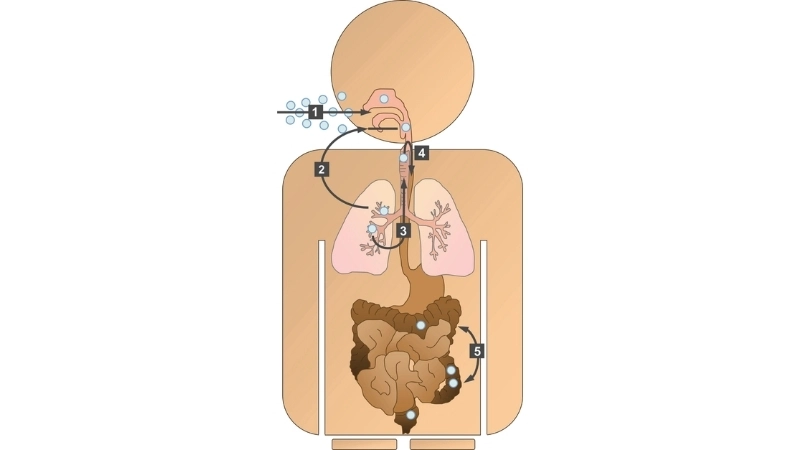

Image description of human bocavirus infection

Human Bocavirus is a small DNA virus causing respiratory infections mainly in children, leading to mild to moderate symptoms such as cough, fever, and fatigue.